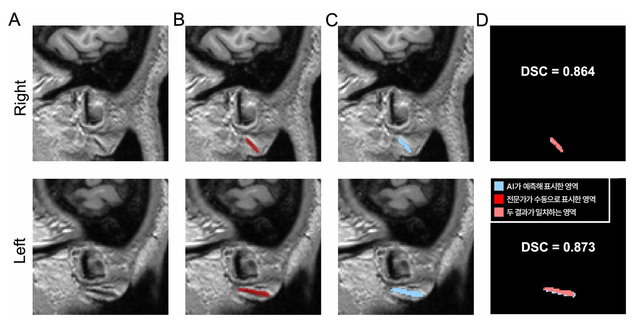

귓불에 사선으로 깊게 파인 주름, 이른바 '프랭크 징후(Frank’s sign)'가 단순한 노화 흔적을 넘어 뇌소혈관 손상 정도를 반영하는 신호일 수 있다는 연구 결과가 나왔다.분당서울대병원 정신건강의학과 김기웅 교수팀은 세계 최초로 3D 뇌 MRI에서 프랭크 징후를 자동 탐지하는 AI 모델을 개발하고 유전성 뇌소혈관질환 환자에서 해당 징후가 뇌백질변성(WMH)의 중증도와 강하게 연관됨을 입증했다고 12일 밝혔다.프랭크 징후는 1973년 미국 의사 샌더스 프랭크가 협심증 환자에서 빈번히 관찰된다고 보고한 이후 심근경색, 뇌졸중, 혈관성 치매 등과의 관련성이 제기돼 왔다. 다만 평가 기준이 표준화되지 않아 관찰자에 따라 판단이 달라지는 한계가 있었다.연구팀은 3D 뇌 MRI에 얼굴과 양쪽 귓불이 함께 촬영된다는 점에 착안했다. 분당서울대병원 뇌 MRI 400건을 바탕으로 전문가가 표시한 주름을 학습시켜 AI 모델을 구축했고 분당서울대병원 600건(1차)과 충남대병원·강원대병원·세브란스병원 460건(2차) 다기관 데이터로 검증했다.전문가 수동 표시와 AI 자동 분할의 일치도를 나타내는 DSC(Dice 유사도 계수)는 0.734, 0.714로 의료영상 분야에서 높은 수준을 기록했다. 프랭크 징후의 유무를 구분하는 AUC 역시 모두 0.9 이상으로, 다양한 임상 환경에서도 안정적인 성능을 보였다.연구팀은 AI 모델을 활용해 유전성 뇌소혈관질환 카다실(CADASIL) 환자에서 프랭크 징후의 임상적 의미를 추가 분석했다. 카다실은 단일 유전자 변이로 발생해 뇌백질변성이 특징적으로 나타나는 질환이다.유전자 검사로 확진된 환자 81명과 연령·성별을 맞춘 일반인 54명을 비교한 결과, 프랭크 징후 발생률은 카다실 환자 66.7%, 일반인 42.6%로 유의한 차이를 보였다.연령 등 교란 요인을 통제해도 카다실 환자에서 프랭크 징후가 있을 확률은 4.2배(OR=4.214) 높았다. 또한 환자군 내에서 프랭크 징후가 있는 경우 뇌백질변성 부피가 약 1.7배 컸다.특히 뇌백질변성 부피를 하·중·상위로 나눴을 때 프랭크 징후 발생률이 37.0% → 66.7% → 74.1%로 단계적으로 증가해 징후가 질환 중증도를 반영한다는 점을 뒷받침했다.김기웅 교수는 "논란이 이어졌던 프랭크 징후가 단순 노화의 부산물이 아니라 유전성 뇌소혈관 손상의 정도를 객관적으로 반영한다는 근거를 제시했다"며 "이 징후만으로 진단할 수는 없지만, 다른 혈관 위험인자가 있다면 전문의 상담을 권한다"고 말했다.한편 이번 연구는 보건복지부·한국보건산업진흥원 보건의료기술연구개발사업과 치매극복연구개발사업단의 지원으로 수행됐으며 국제학술지 Scientific Reports와 Journal of Clinical Medicine에 각각 게재됐다.